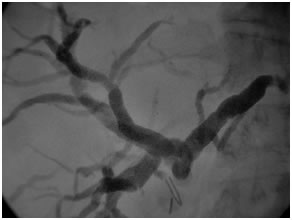

PTBD gram showing type II biliary stricture

Post operative PTBD gram showing a patent high hepaticojejunostomy